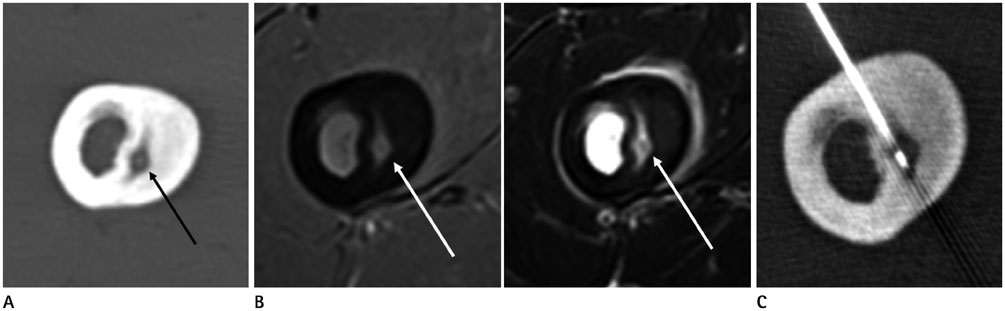

Efficacy of Computed Tomography Guided Radiofrequency Ablation for Osteoid Osteomas in 31 Patients

To present the clinical outcome of computed tomography (CT) guided radiofrequency ablation (RFA) for osteoid osteoma.

Thirty-one patients (M:F = 23:8, mean age: 20 years, range: 4-54 years) who underwent RFA for clinically suspected osteoid osteoma from May 2004 to December 2013 were retrospectively reviewed. RFA was done in all cases under CT guidance by one of three radiologists in our department. Electronic medical records and images were retrospectively reviewed in all patients.

CT-guided RFA is an effective method for the treatment of osteoid osteoma.